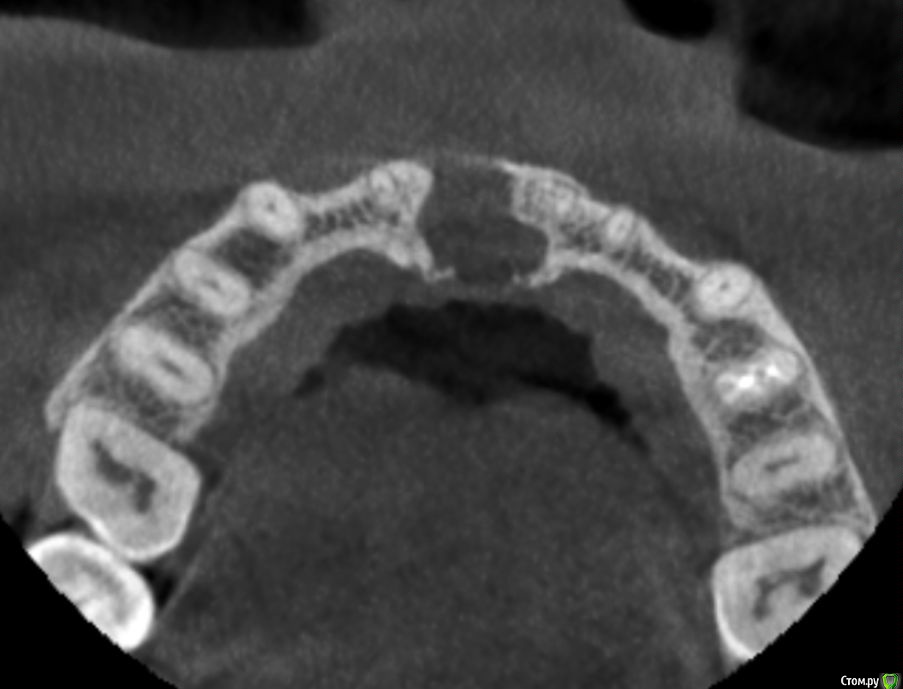

Kazankov.Egor Опубликовано 6 июля, 2018 Поделиться Опубликовано 6 июля, 2018 (изменено) Жалобы на неприятный запах изо рта, предположительно от 11 зуба. В анамнезе РВК 11 зуба.Скрины кт прилагаю. Пациент девушка, естественно, главный вопрос -эстетика. Нужна помощь по тактике. Изменено 6 июля, 2018 пользователем Kazankov.Egor Ссылка на комментарий

Kazankov.Egor Опубликовано 7 июля, 2018 Автор Поделиться Опубликовано 7 июля, 2018 Визуально, небольшая рецессия десны, кариес цемента. Ссылка на комментарий

Kazankov.Egor Опубликовано 7 июля, 2018 Автор Поделиться Опубликовано 7 июля, 2018 Если зуб под коронкой не сгнил, то ревизия периапикальных тканей и ретроградная пломбировка канала.А с кистой несонобного канала как поступить? Ссылка на комментарий